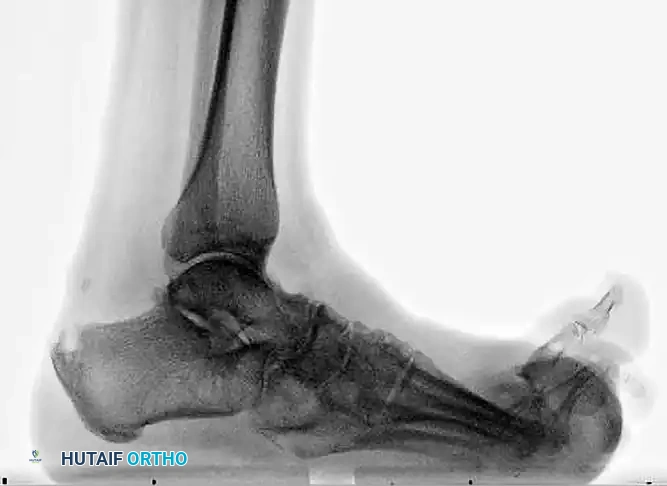

The following preoperative and postoperative radiographs demonstrate the successful application of augmented fixation in a young diabetic patient with a severe bimalleolar fracture-subluxation:

FIGURE 85-25 A and B: Preoperative radiographs of a highly unstable bimalleolar ankle fracture-subluxation in a 19-year-old man with a 12-year history of insulin-dependent diabetes mellitus.

FIGURE 85-25 C-E: Postoperative fixation demonstrating robust fibular plating, medial malleolar screw fixation, and critical supplemental syndesmotic screws to reinforce the mortise.